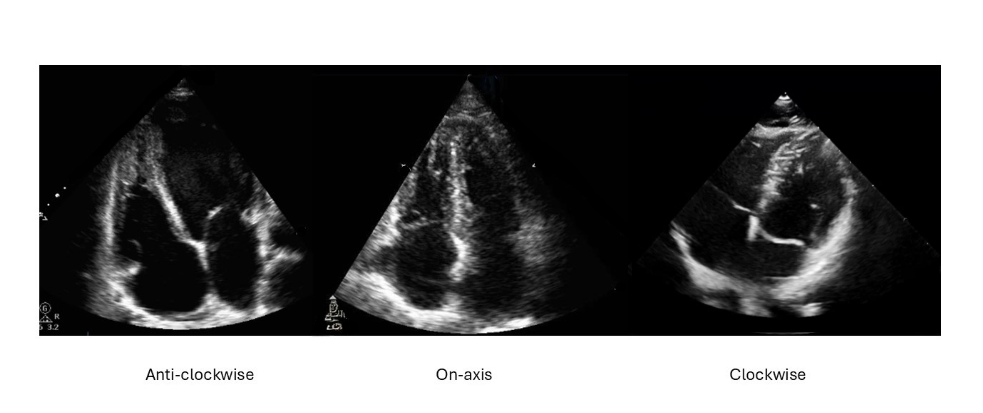

Visual Examples

Rotation examples